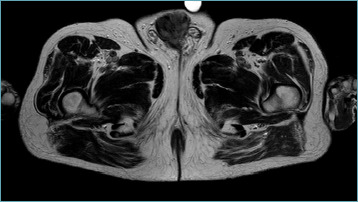

Results: Our series refers to the 30-year experience of highlighting the heterogeneity in the presentation and microscopic features of these rare sarcomas. 18 penile soft tissue tumours are described, 4 benign and 14 malignant. The mean age at diagnosis was 58.2 years (range 24-96 years) and 53.6 years among malignancies (range 24-89). The most frequent histotype was Kaposi's sarcoma (nr = 4) and very unusual histotypes were observed, namely low-grade fibromyxoid sarcoma, synovial sarcoma, proximal type epithelioid sarcoma and the first reported case of dedifferentiated liposarcoma of the penis.

Conclusions: Among sarcomas of the genitourinary tract, tumours of the soft tissues of the penis are the rarest. Penile sarcomas can present at a young age. Kaposi's sarcoma in HIV-negative patients has a favorable outcome, while deep sarcomas have an aggressive behavior and poor prognosis.